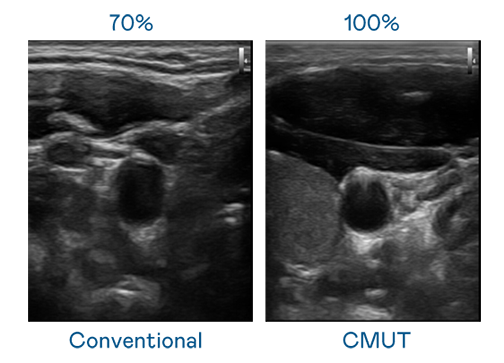

CMUT 技术是一种用电容式微机电元件来产生超音波讯号的技术。与传统 PZT 压电式技术相比,CMUT 频宽增加 30%,更宽频的超音波讯号让影像解析度大幅提升,是实现高影像品质医疗超音波扫描、促进精准医疗发展的关键技术。

大频宽带来超清晰影像

超音波影像的解析度高低,首先取决于探头能发出的讯号频宽。AG一飞冲天 CMUT 可提供高清晰的超音波讯号,提供高频宽、高灵敏度、影像纹理细节更高的超音波影像,协助医护人员缩短影像判读时间及利用精准的医疗影像进行诊断。